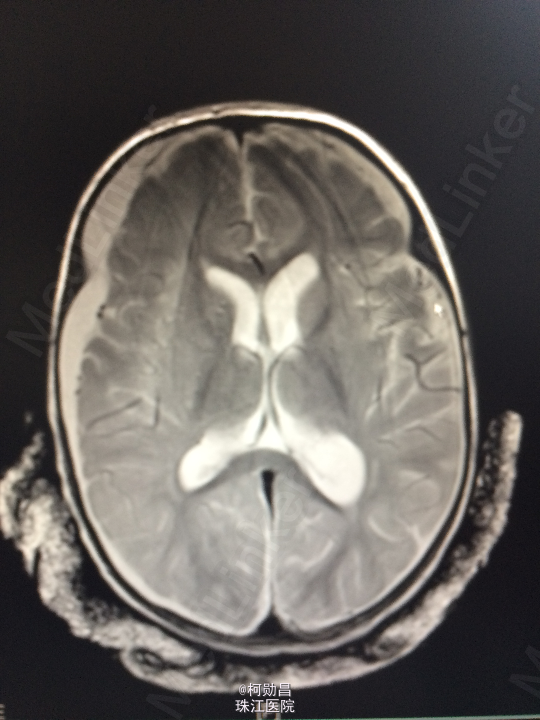

主诉:发热10天,抽搐3天 病史:患儿出生后8个月,因“发热10天,抽搐3天”入院,入院时体温39.3℃,神志不清,反应差。四肢肌张力增高,以双上肢肌力增高明显。病理征未引出。

查体:神志不清,四肢肌力增高 辅助检查:头颅CT提示脑积水并脑脊液外渗,幕上脑室扩张,右侧额颞叶硬膜下脑脊

诊断:化脓性脑膜炎伴脑积水 处理:予内科抗感染治疗,后行脑室腹腔引流术。